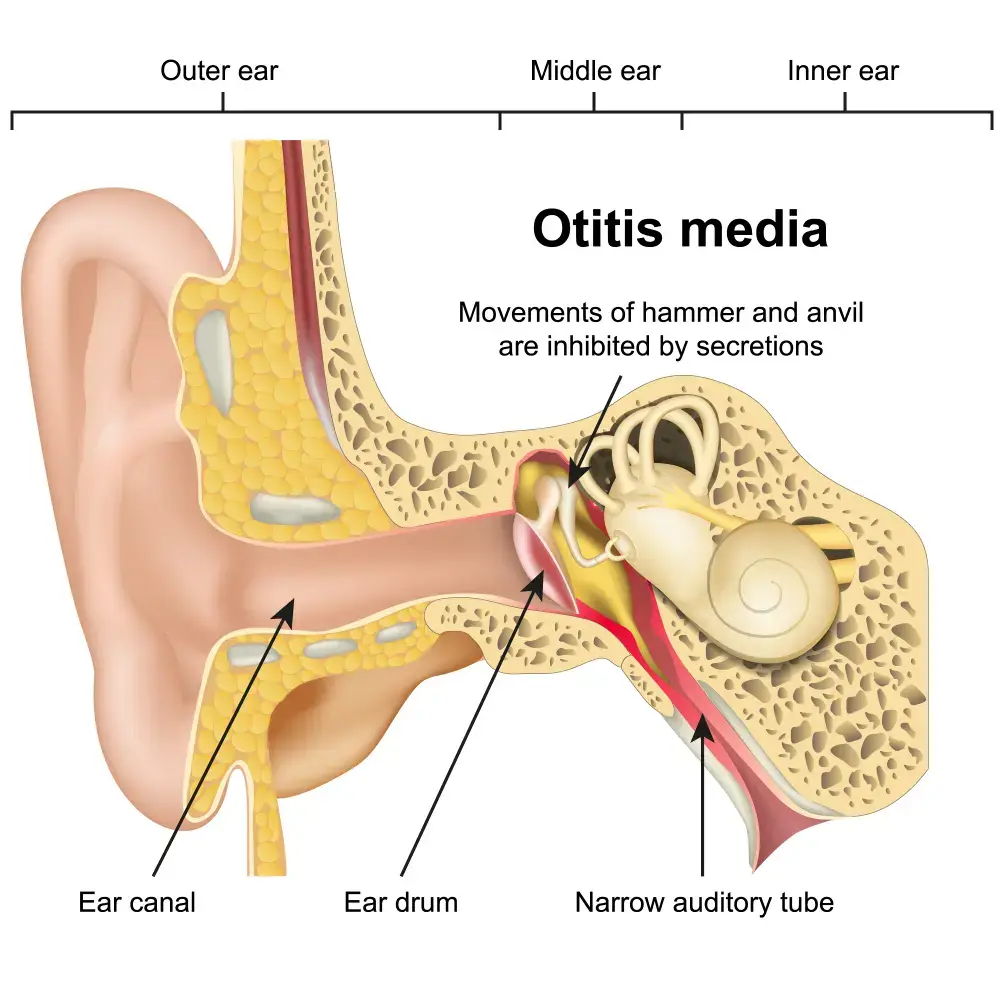

Pediatric Otitis Media (OM): Babies and Children

Otitis Media (OM) is a common pediatric illness that most often affects young children. It occurs when the middle ear becomes infected with bacteria.

Symptoms include severe pain, fever, and hearing loss in one or both ears. Otitis media (OM) can be serious and require treatment, but it can usually be resolved with antibiotics.

There is no known cause of Otitis media (OM), but it is believed to be caused by a combination of factors including viral infections, allergic reactions, and environmental exposures.

This is a common childhood illness that can lead to long-term hearing problems in some cases.